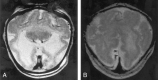

Background and purpose: Analysis of specific features in the brain of patients with holoprosencephaly (HPE) may clarify normal and abnormal brain development and help predict outcomes for specific children. We assessed sulcal and gyral patterns of cerebral cortex in patients with HPE and developed a method of grading brain development.

Methods: Neuroimaging studies (75 MR imaging, 21 CT) of 96 patients with HPE were retrospectively reviewed, with specific attention paid to the cerebral cortex. Thickness of cortex, width of gyri, and depth of sulci were assessed subjectively and by measurement. The angle between lines drawn tangential to the sylvian fissures ("sylvian angle") was measured in each patient with HPE and in 20 control patients.

Results: Thickness of cortex was normal in all 96 patients. Gyral shape and width and sulcal depth were normal in 80 patients. Twelve patients, all with very severe HPE and microcephaly, had reduced sulcal depth, diffusely in eight and limited to the anteromedial cortex in four with lobar HPE. Four patients had subcortical heterotopia, located anterior to the interhemispheric fissure, associated with shallow sulci in the overlying cortex. Sylvian fissures were displaced further anteriorly and medially as HPE became more severe, until, in the most severe cases, no sylvian fissures could be identified. Sylvian angle measurements corresponded closely with severity of HPE, being largest in the most severe and smallest in the least severe cases. All patients with HPE had sylvian angles significantly larger than the mean of 15 degrees measured in the control patients.

Conclusion: The only true malformations of cortical development were subcortical heterotopia. However, diffuse and focal abnormal sulci were observed. We propose our sylvian angle measurement of extent of frontal lobe development as an objective means of quantifying the severity of HPE.